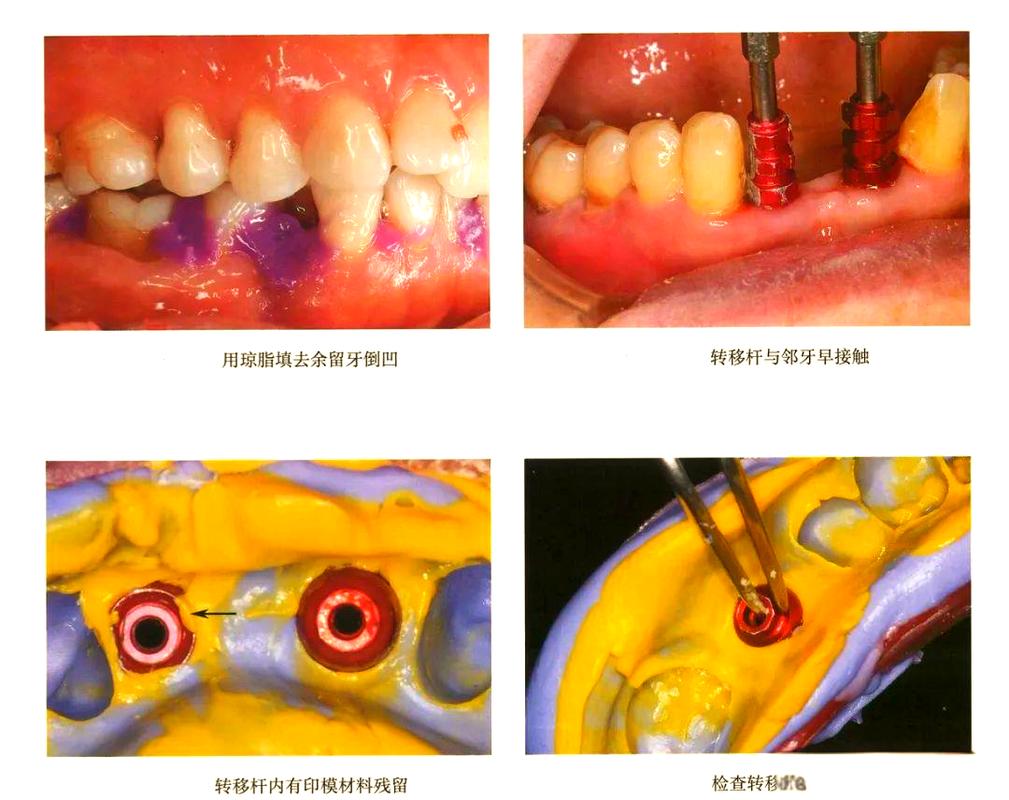

- 原理: 在种植体完全骨结合后,先安装转移杆,取一个初步印模(通常使用开放托盘或简易托盘),然后从初步印模中取出带有转移杆的工作模型,在工作模型上安装替代体(Analog),最后将替代体连同转移杆一起放回口腔,使用个性化印模托盘进行最终印模。

- 优点: 对种植体上方基台高度要求较低(即使基台很低也可以);可以更精确地记录种植体周围软组织形态(如龈沟形态、位置),尤其适用于前牙美学区或需要精确复制软组织轮廓的病例;工作模型上可进行复杂的设计和调整。

- 特点: 操作简单快捷,成本较低,但精度相对较低,尤其在记录种植体位置和角度时,材料容易流动或产生气泡,对操作者技术要求较高,常用于二次法中的初步印模。